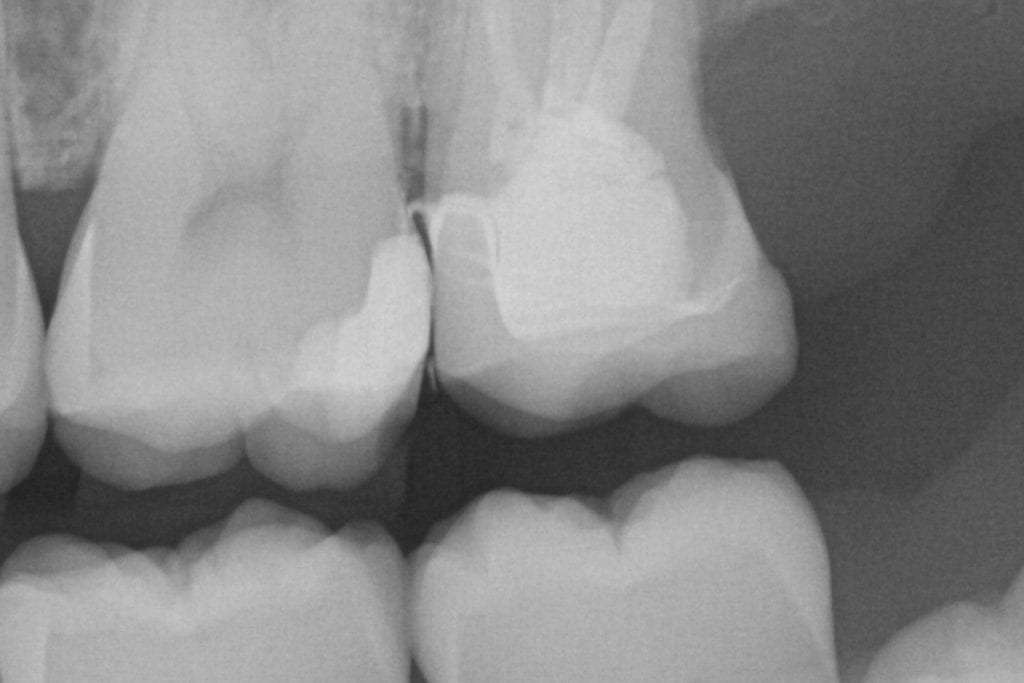

It was a long struggle to find margins with the Omnicam and after 4 years it was sold. The margin definition and resolution never reached an acceptable level. After seeing margins from high resolution scans by the Medit and defining them in exocad, it completely validated that we shouldn’t settle for anything less than the highest standard. This is an scan performed on a upper second molar with tough access, replacing a failing crown.

LAST X-RAY IS IMMEDIATE POST OP- EXCESS CEMENT WAS REMOVED AFTER FILM CHECK